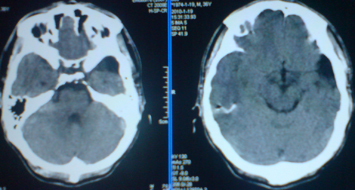

标题: CT24297:患者,男,左手抽搐致摔倒,平时无不适。 [打印本页]

标题: CT24297:患者,男,左手抽搐致摔倒,平时无不适。

外侧裂池蛛网膜囊肿或神经上皮囊肿,左侧颞顶叶脑萎缩。

上皮囊肿,左侧颞顶叶脑萎.

1)左侧颞顶叶脑萎缩。2)左侧外侧裂池蛛网膜囊肿?

考虑先天性左脑发育不良

脑软化灶 脑萎缩.

外侧裂池蛛网膜囊肿,左侧颞顶叶脑萎缩。

1.左侧顶叶脑软化并脑脑穿通畸形,左侧大脑半球萎缩。2.左侧外侧裂蛛网膜囊肿。